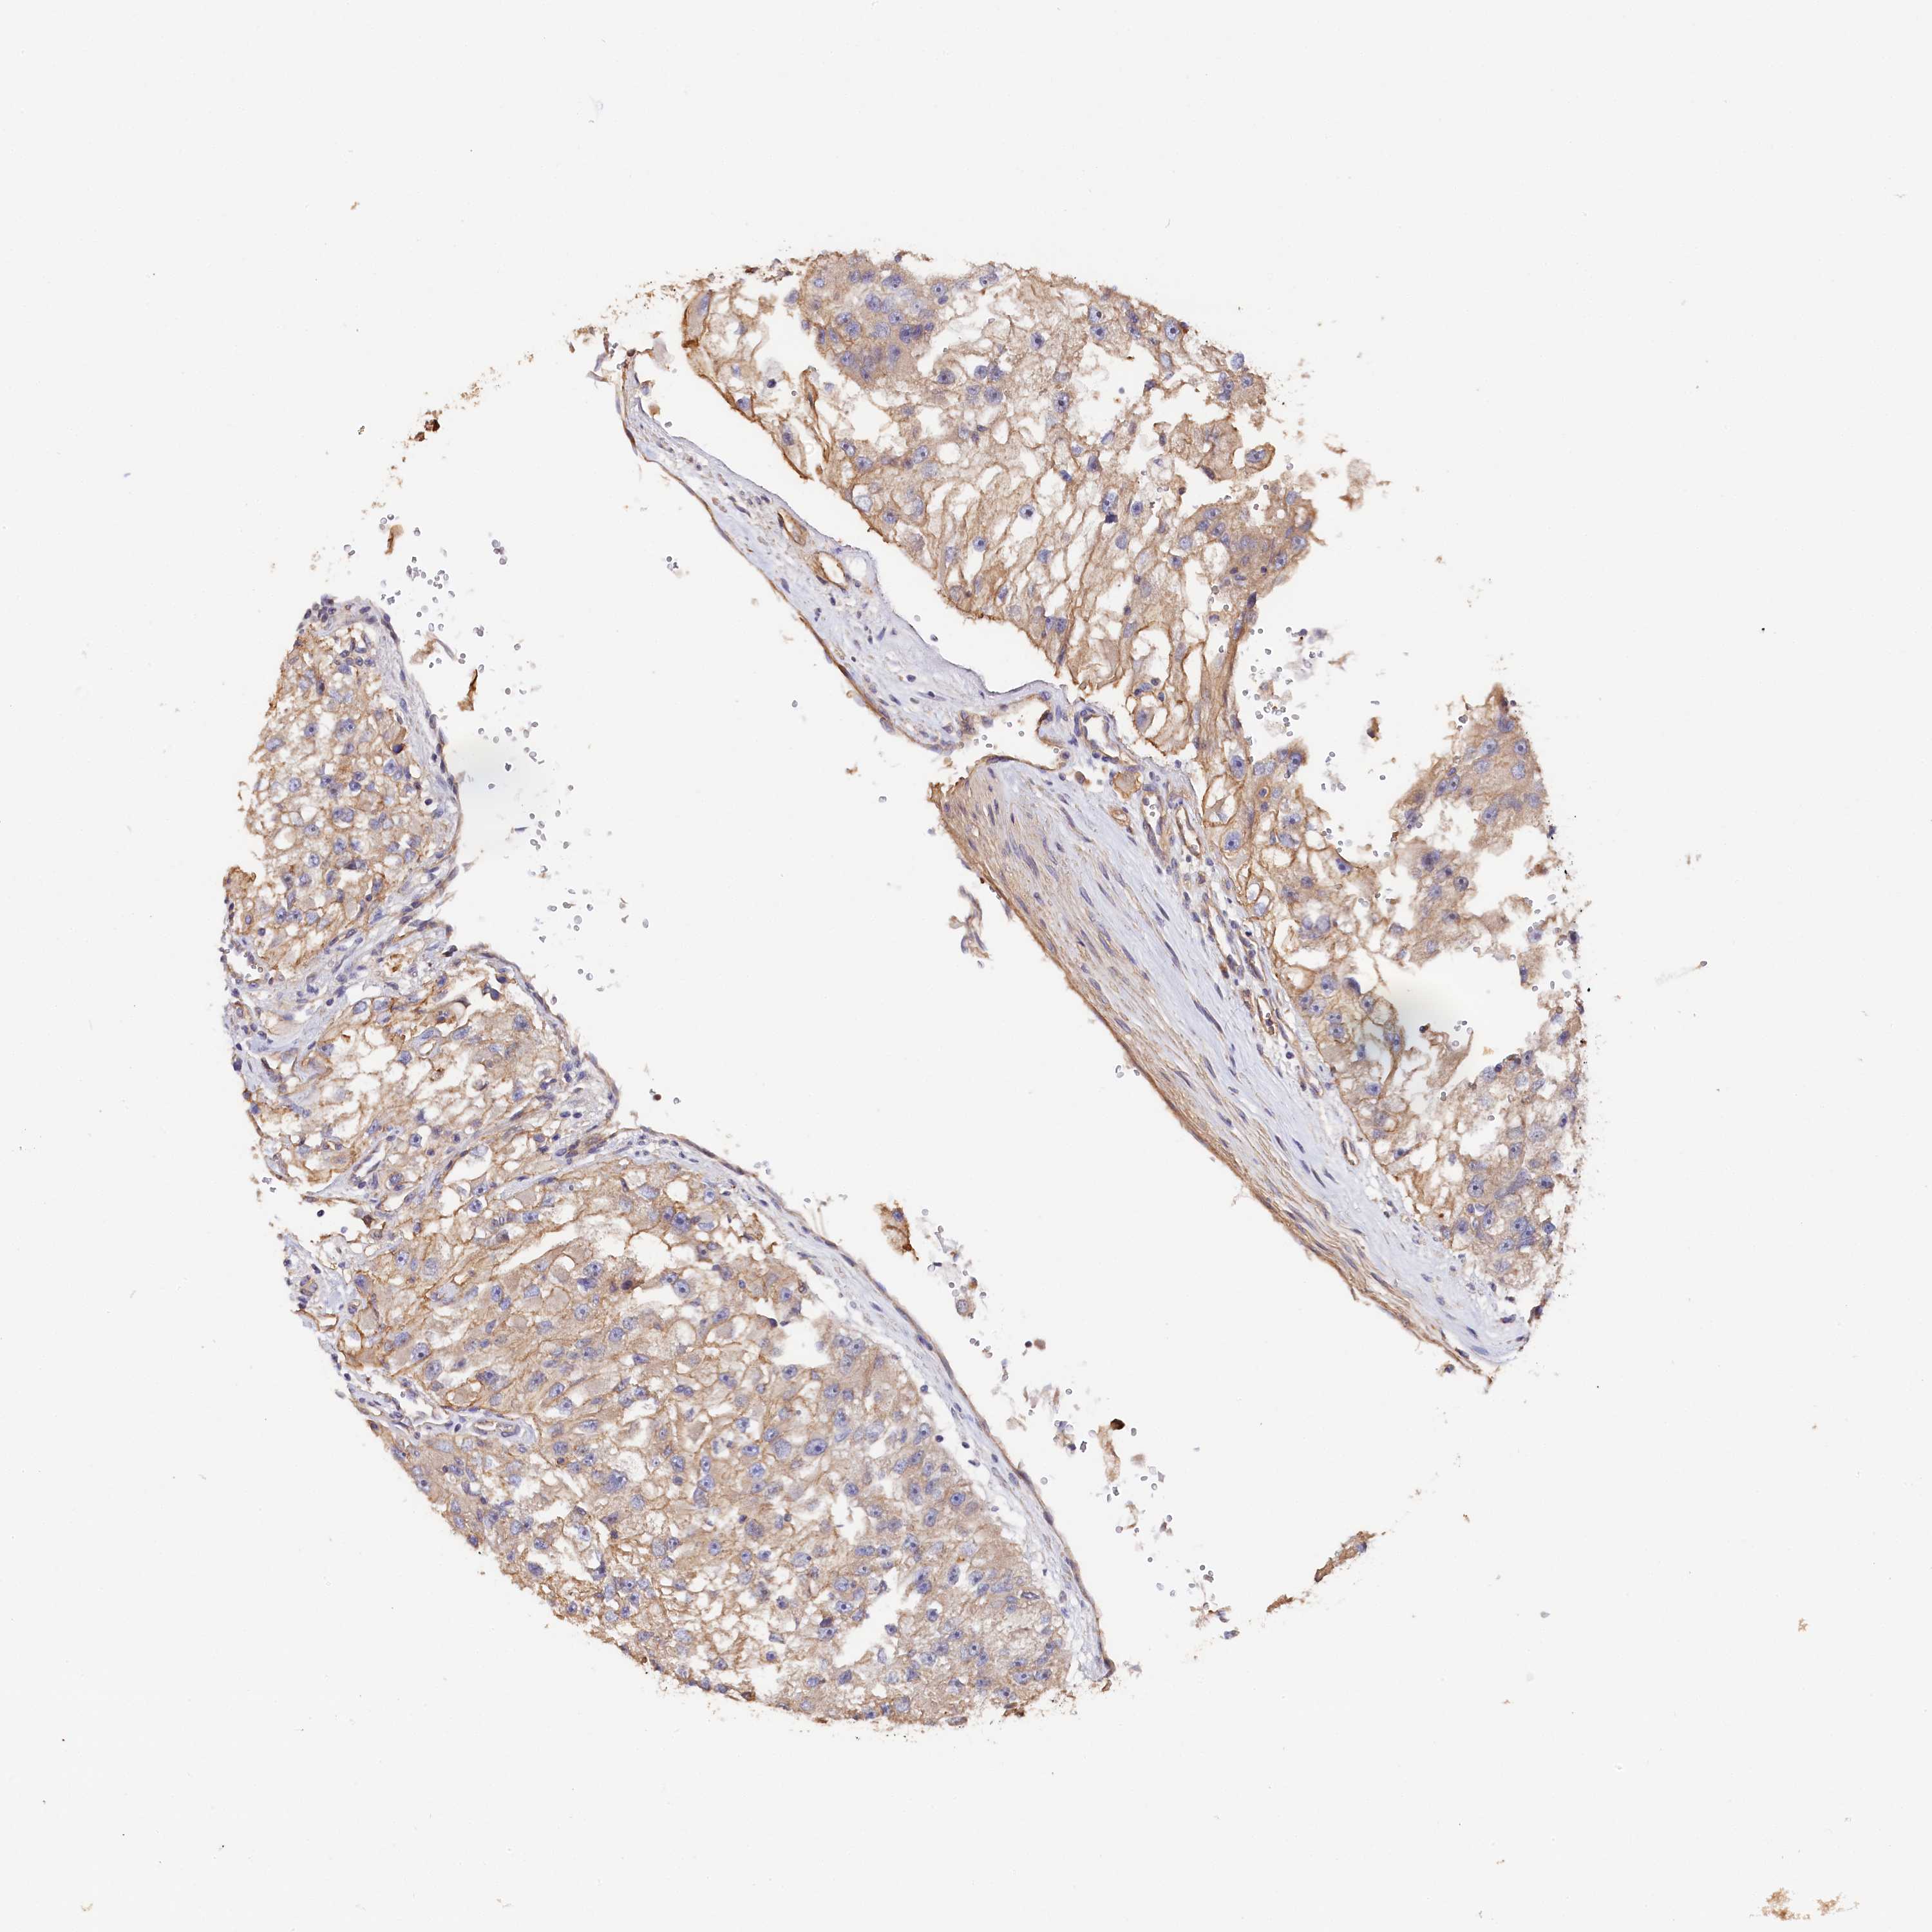

KIDNEY RENAL CLEAR CELL CARCINOMA (VALIDATION) - Interactive survival scatter ploti

The Survival Scatter plot shows the clinical status (i.e. dead or alive) for all individuals in the patient cohort, based on the same data that underlies the corresponding Kaplan-Meier plots. Patients that are alive at last time for follow-up are shown in blue and patients who have died during the study are shown in red.

The x-axis shows the expression levels (FPKM) of the investigated gene in the tumor tissue at the time of diagnosis. The y-axis shows the follow-up time after diagnosis (years). Both axes are complimented with kernel density curves demonstrating the data density over the axes. The top density plot shows the expression levels (FPKM) distribution among dead (red) and alive patients (blue). The right density plot shows the data density of the survived years of dead patients with high and low expression levels respectively, stratified using the cutoff indicated by the vertical dashed line through the Survival Scatter plot. This cutoff is automatically defined based on the FPKM cutoff that minimizes the p-score. The cutoff can be changed by dragging the vertical line or by entering a cutoff value in the square labeled "Current cut-off".

Under the Survival Scatter plot the p-score landscape (black curve; left axis) is shown together with dead median separation (red curve; right axis). Dead median separation is the difference in median mRNA expression between patients who have died with high and low expression, respectively. It is calculated as follows: median FPKM expression of dead patients with high expression - median FPKM expression of dead patients with low expression. This is intended to aid the user in visually exploring custom cutoffs and the associated p-scores and dead median separation.

Individual patient data is displayed and can be filtered by clicking on one or more of the category buttons on the top of the page. Categories describing expression level and patient information include: high, low, alive, dead, female, male and tumor stages. The scale of the x-axis can be toggled between linear and log-scale by clicking on the "x log" button. Mouse-over function shows TCGA ID, patient information and mRNA expression (FPKM) for each patient.

& Survival analysisi

Kaplan-Meier plots summarize results from analysis of correlation between mRNA expression level and patient survival. Patients were divided based on level of expression into one of the two groups "low" (under cut off) or "high" (over cut off). X-axis shows time for survival (years) and y-axis shows the probability of survival, where 1.0 corresponds to 100 percent.

KATNB1 is not prognostic in Kidney Renal Clear Cell Carcinoma (validation)

Best expression cut offi

Based on the FPKM value of each gene, patients were classified into two groups and association between prognosis (survival) and gene expression (FPKM) was examined. The best expression cut-off refers the FPKM value that yields maximal difference with regard to survival between the two groups at the lowest log-rank P-value. Best expression cut-off was selected based on survival analysis .

When clicking on this number, the vertical dashed line indicating cut-off, the interactive survival plot, and the Kaplan-Meier curve will be adjusted to show results based on the best expression cut-off.

: 17.64

Median expressioni

Median expression refers to the median FPKM value calculated based on the gene expression (FPKM) data from all patients in this dataset. When clicking on this number, the vertical dashed line indicating cut-off, the interactive survival plot, and the Kaplan-Meier curve will be adjusted to show results based on the median expression.

: N/A

Median follow up timei

Median follow up time refers to the median time (years) after diagnosis with this type of cancer, based on clinical data from all patients in this dataset.

P scorei

Log-rank P value for Kaplan-Meier plot showing results from analysis of correlation between mRNA expression level and patient survival.

N/A

5-year survival highi

5-year survival for patients with higher expression than the expression cutoff.

For melanoma and glioma, 3-year survival is shown.

5-year survival lowi

5-year survival for patients with lower expression than the expression cutoff.

TCGA RNA samplesi

RNA-seq data is reported as average FPKM (number Fragments Per Kilobase of exon per Million reads), generated by the The Cancer Genome Atlas (TCGA) .

Normal distribution across the dataset is visualized with box plots, shown as median and 25th and 75th percentiles. Points are displayed as outliers if they are above or below 1.5 times the interquartile range. FPKM values of the individual samples are presented next to the box plot.

Average pTPM 14.4

Number of samples 100